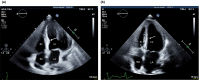

A primigravida 26-year-old woman who had developed pre-eclampsia with malignant hypertension at 30 weeks of gestation suffered acute myocardial infarction two days postpartum. Electrocardiogram demonstrated diffuse ST-segment depression suggestive of subendocardial ischemia. Echocardiography demonstrated focal asymmetric left ventricular hypertrophy, with a characteristic "basal septal bulge", and a left ventricular mid-cavitary gradient of 51 mmHg. Coronary angiography revealed normal coronary arteries and vascular flow. Peripartum acute myocardial infarction is rare and portends a high mortality. However, to date, only one case of acute myocardial infarction associated with asymmetric left ventricular hypertrophy and pre-eclampsia has been described in the literature.